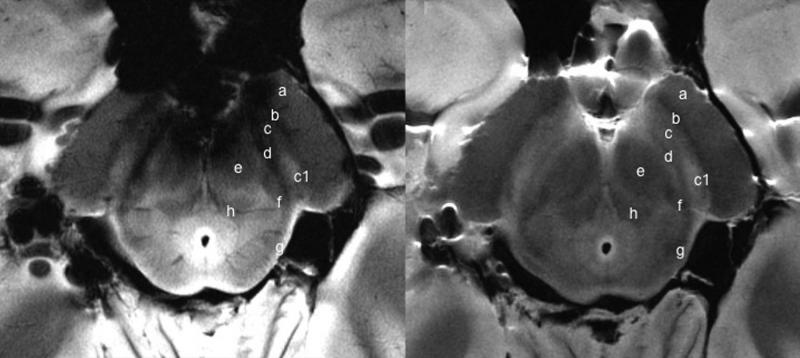

Using the 7-T MRI, the researchers were able to distinguish a three-layered organization of the substantia nigra (SN), a crescent-shaped mass of cells in the midbrain. Parkinson’s disease results from the loss of dopamine-producing cells located in this region of the brain.

Based on abnormalities in the SN identified by the 7-T MRI, the researchers correctly classified patients with Parkinson’s disease with a sensitivity of 100 percent and specificity of 96.2 percent.